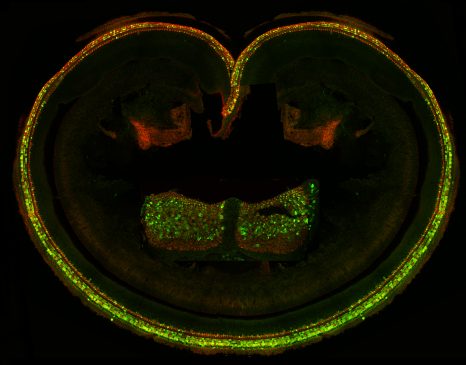

« Ressusciter » les neurones du nerf optique

Vision